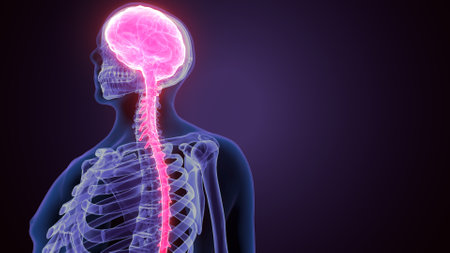

Digital illustration of human skull with glowing brain in profile view

This artistic visualization depicts the human anatomy, highlighting the brain, spine, and nervous system in vibrant red hues. Aimed at educational and medical audiences, this model enhances comprehension of human physiology.

3D Illustration Concept of Central Organ of Human Nervous System Brain Anatomy

3D Illustration Concept of Central Organ of Human Nervous System Brain Anatomy

Detailed anatomical illustration depicting the human spine and nervous system connected to the brain, suitable for educational materials in health and science fields.